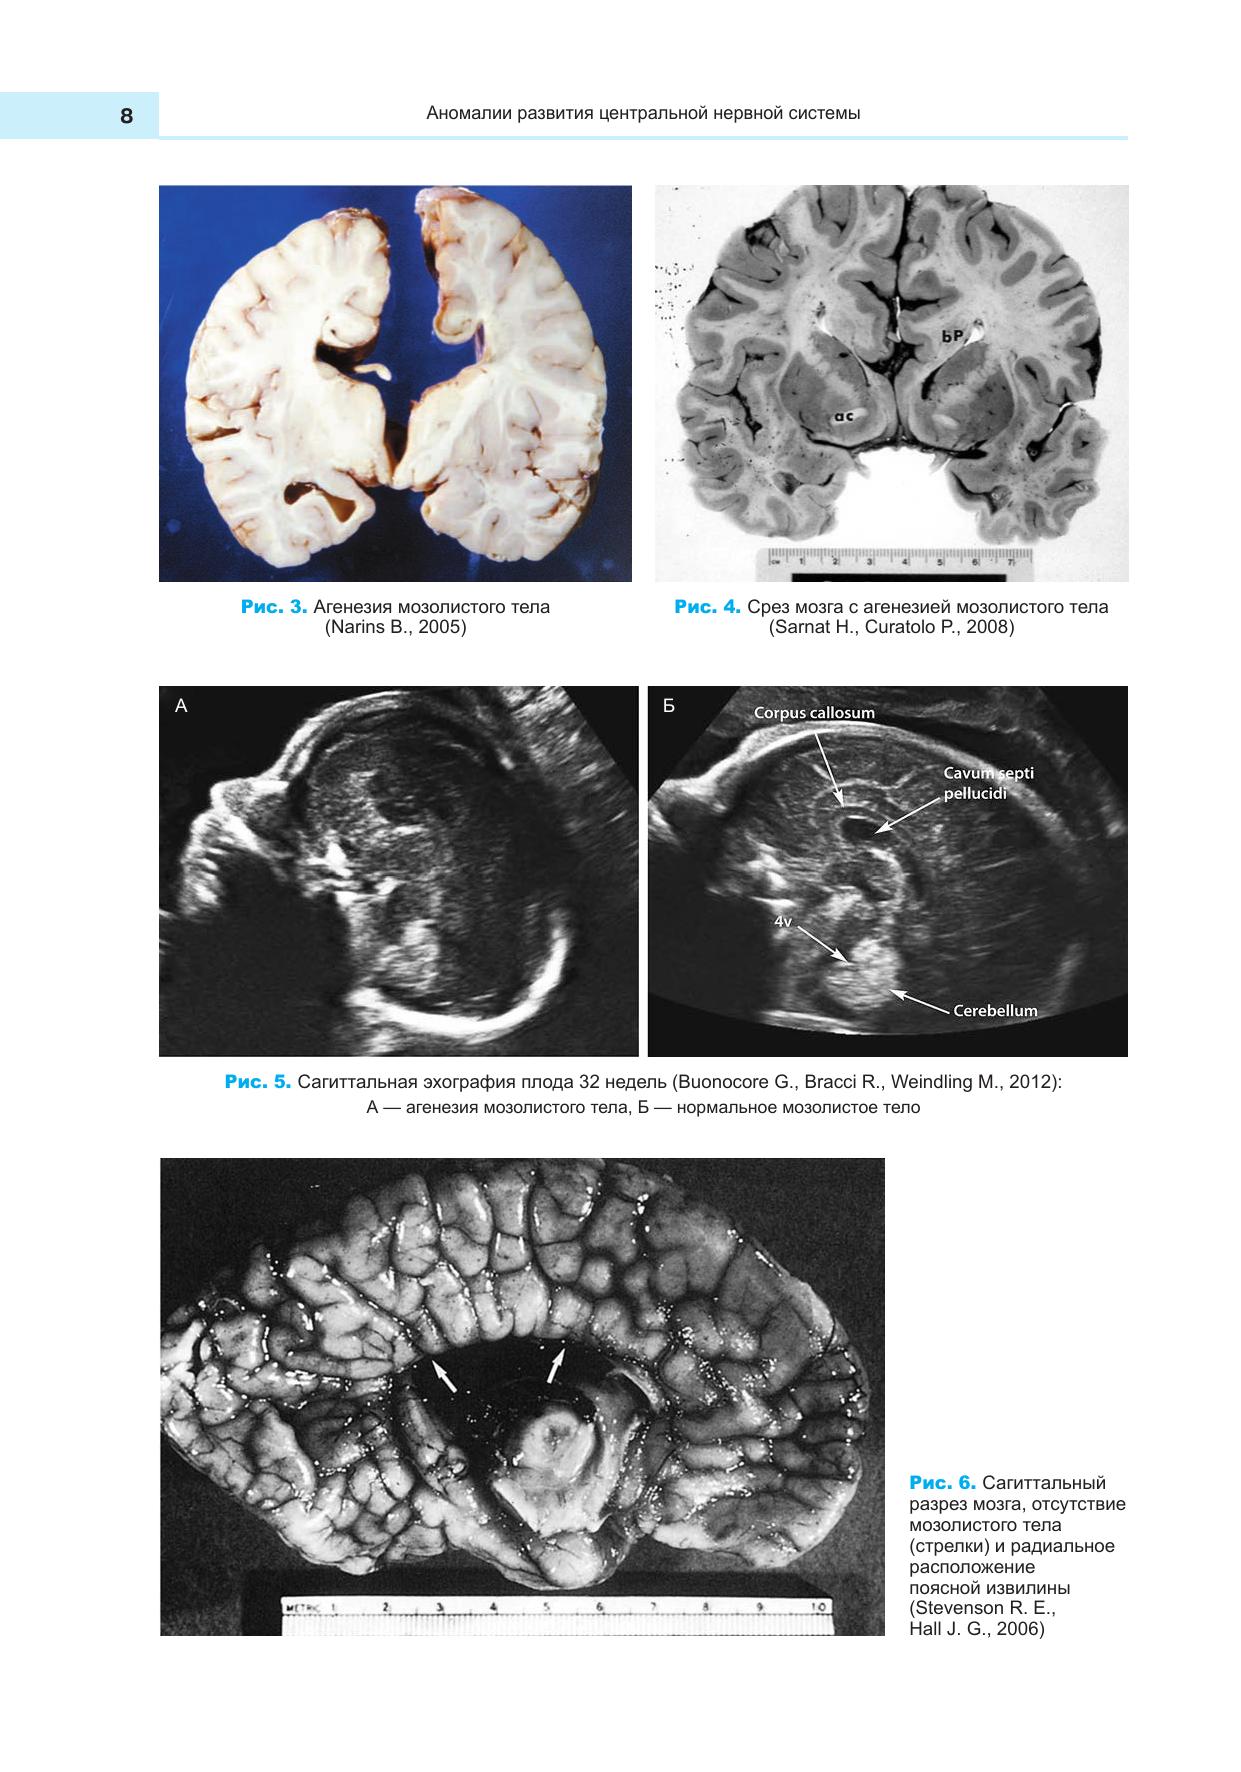

Пособие содержит краткое описание пороков и аномалий развития центральной нервной и сердечно-сосудистой систем человека, систематизированных на основе международной классификации пороков развития ВОЗ и международной статистической классификации болезней и причин, связанных со здоровьем. Пособие содержит большое количество иллюстративного материала. Учебное пособие предназначено для студентов ссузов. Соответствует современным требованиям Федерального государственного образовательного стандарта среднего профессионального образования и профессиональным квалификационным требованиям.